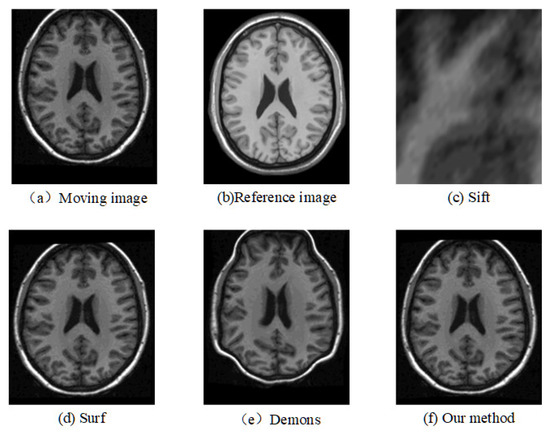

The registration results of the two datasets are shown in Table 1 and Table 2. Moreover, we randomly select two slices based on CUMC12, shown in Figure 6 and Figure 7, and those based on MGH10, shown in Figure 8 and Figure 9.

The corresponding relationship of spatial location can be seen in Figure 6 to Figure 9 between moving image and the reference image. These figures show lots of differences between the moving image and the reference image, including the significant shift of location, different size, the respective concavity and convexity of cerebral cortex, and different degree of smoothness. After registration, the results of our method are the closest to the reference image in multiple aspects, such as spatial location, image size, and brain contour. Surf is second-best, and close to the reference image for the spatial location and size. However, it represented the distortion in the contour of the cerebral cortex to some extent (as shown in Figure 6), and the skewing for some slices (as shown in Figure 8) after registration. The results of the Demons are totally different from the reference image in the spatial location, image size, and contour of the cerebral cortex. It also showed great distortion and deformation. Sift is the worst algorithm, and its current result did not show the brain shape.

Figure 6. Registration results of any one slice from any T1 image based on CUMC12 dataset.